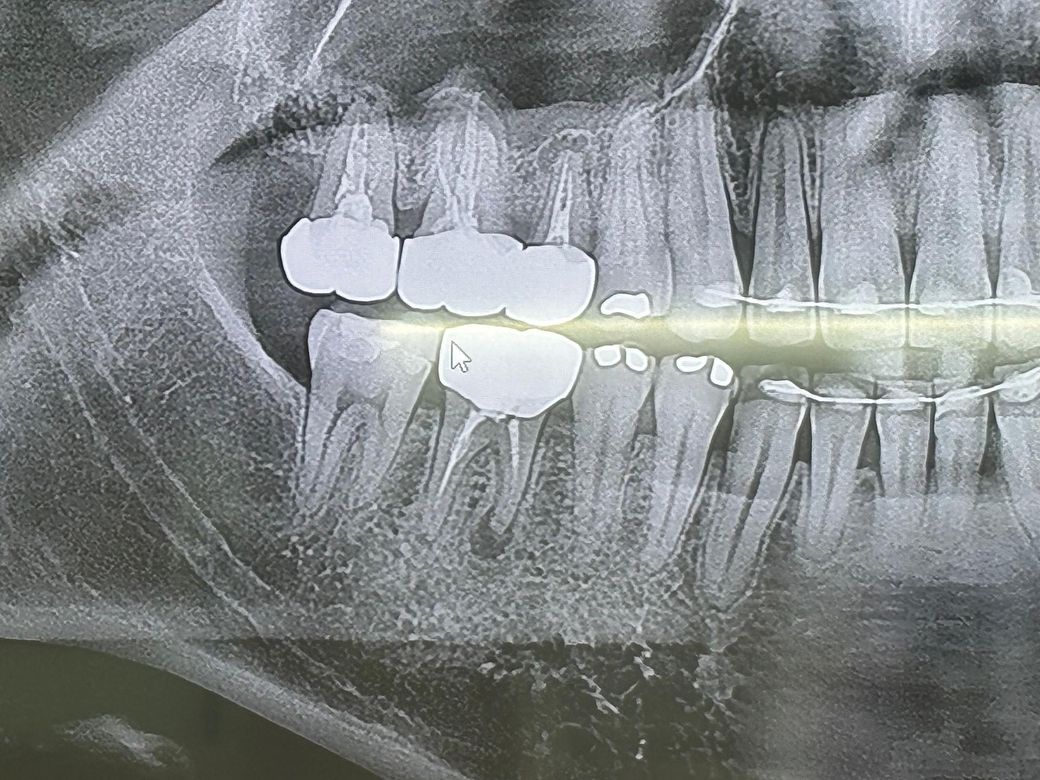

• 1번 째 사진

1. 뿌리끝 염증이 있는 것은 엑스레이상 너무 명확합니다.

말씀하신 부분의 치아의 뿌리 끝에 염증이 있어 보입니다. 만약에 해당 부분의 염증이 커지지 않고 있는다면 꼭 치료를 하지 않아도 되나 주기적으로 치과를 방문하여 검진은 하셔야 합니다. 다만 대부분은 해당 부분의 염증이 커지게 되어 문제를 일으키게 되어 발치를 하거나 재신경치료를 해야하는 경우도 많습니다.